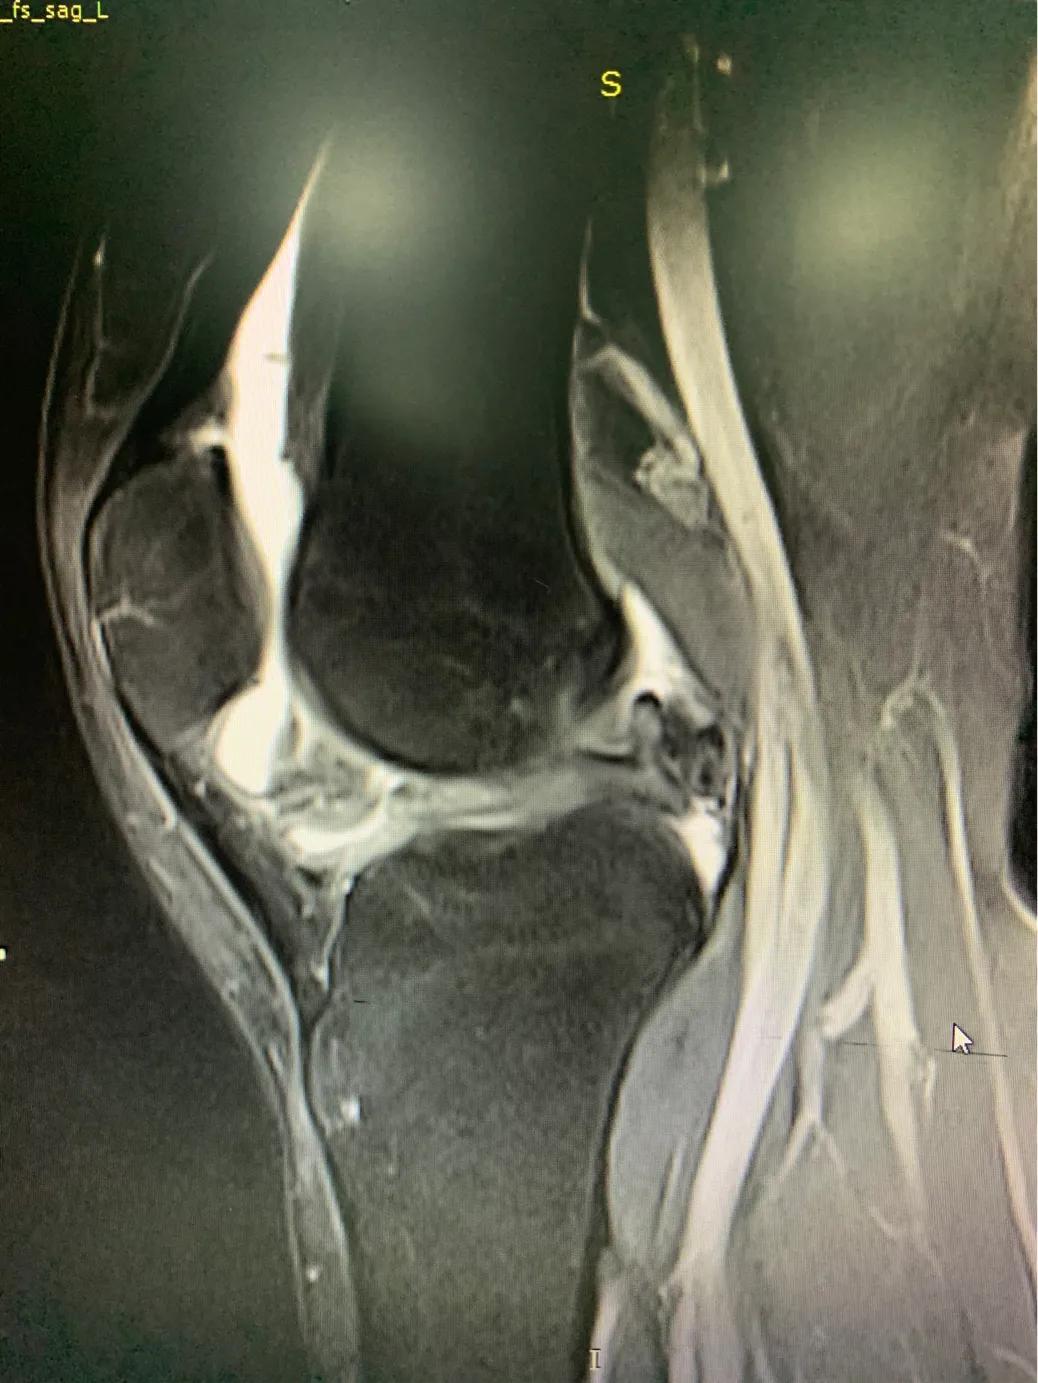

半月板损伤的磁共振